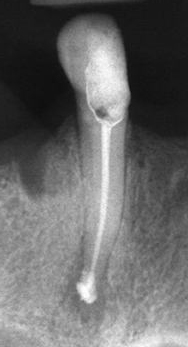

Запълване с препресване

Ендодонтия